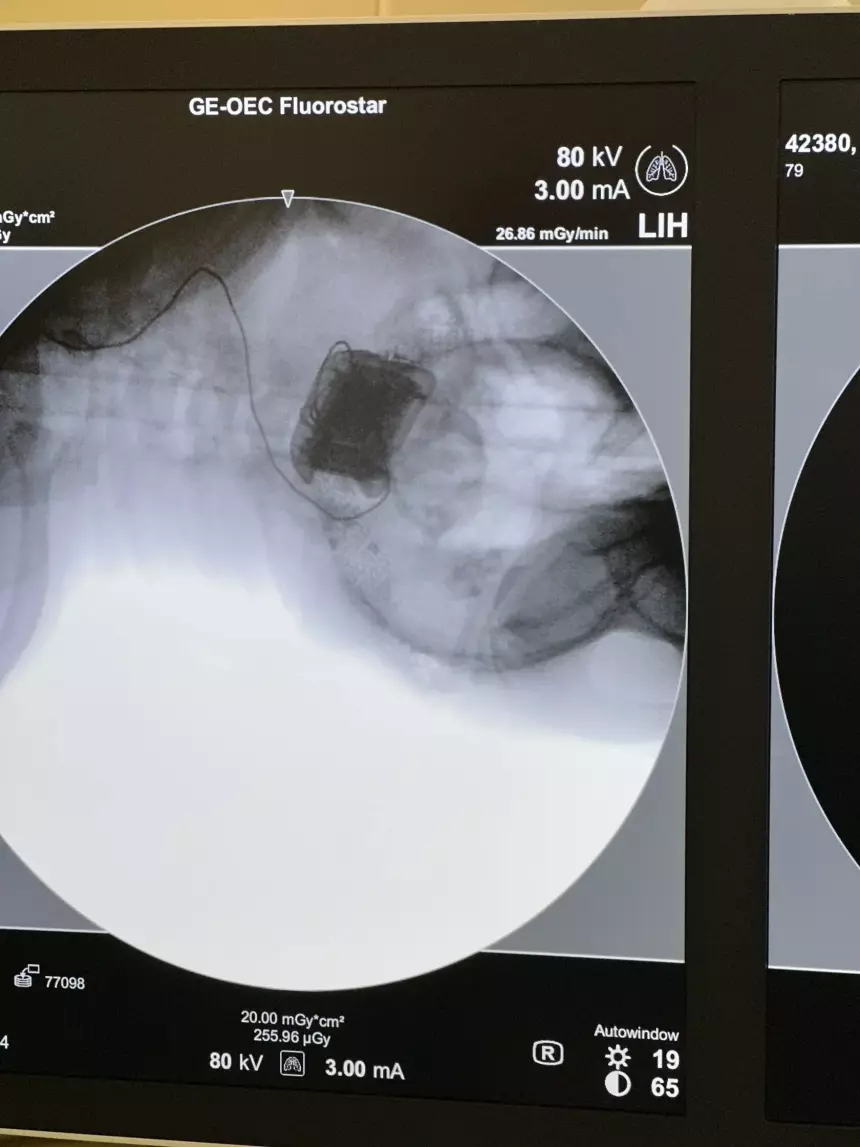

Железо в черепе и беспроводная передача энергии сквозь кожу

Имплантация чипа представляет собой ювелирную нейрохирургическую операцию. В затылочной части черепа хирург делает небольшое отверстие, куда устанавливается электронный блок в сверхнадежном титановом корпусе, полностью совместимом с биологическими тканями. От этого блока отходит матрица с десятками микроскопических электродов, которые проникают в первичную зрительную кору мозга на глубину нескольких миллиметров. Именно эти электроды будут бить по нейронам слабыми, строго выверенными электрическими токами величиной в микроамперы.